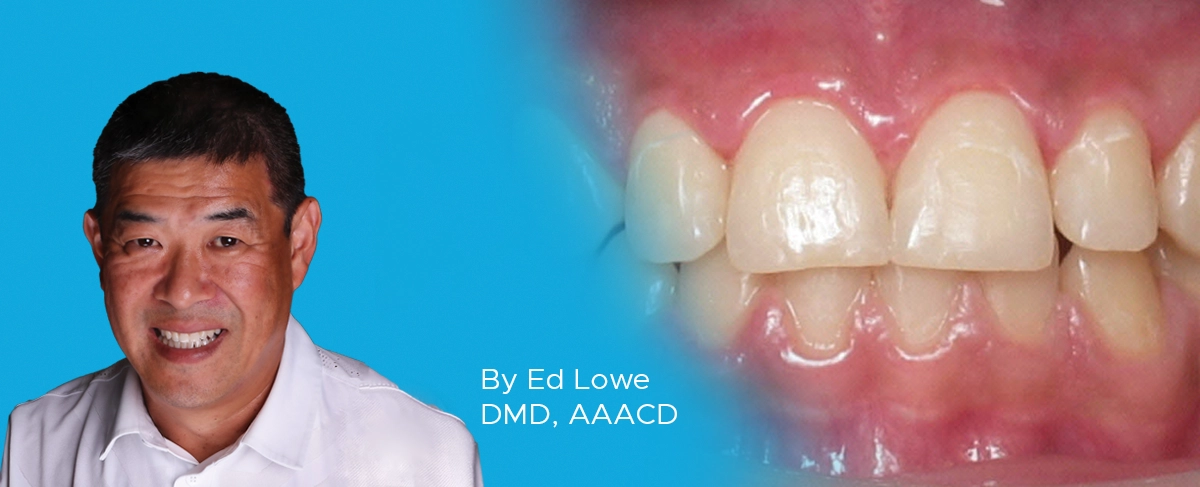

This scenario can create a time-management headache in a busy clinical setting. In this case of a fractured crown (FIG. 1) where a portion of the crown remains cemented on a vital tooth, the patient was experiencing sensitivity due to exposed dentin and required immediate temporary coverage.

Patient presented as an emergency patient with a fractured ceramic crown. The tooth was vital and the patient was experiencing sensitivity due to exposed dentin.

In any clinical setting, available chair time may be limited and may not allow for obtaining an impression of the fractured tooth along with the opposing dentition and fabricating a temporary matrix from an ideal wax-up. Therefore, the clinician may build up the tooth with old or expired composite or wax and then take an impression of the tooth. One challenge with this method, however, is that the composite or wax buildup may dislodge from the tooth in the process of taking the impression of the tooth. In order to avoid this another technique was utilized. An impression of the non-intact tooth was taken using Template Ultra Quick Matrix Material (Clinician’s Choice) in a Quad-Tray Xtreme (Clinician’s Choice) dual-arch impression tray. (FIG 2)

The remaining restoration was then removed from the impression using a bur in order to provide room for a full thickness temporary. It was necessary to perforate the temporary impression in order to gain sufficient space. (FIG. 3)

The areas of the missing crown structure were removed with a rotary instrument. It is important that sufficient material is removed to allow for adequate thickness of temporary material.

At this point, the temporary impression was set aside until the tooth was re-prepared for the new restoration. Once the temporary crown was fabricated using Inspire Esthetic Provisional Composite (Clinician’s Choice), it was necessary to quickly recontour and establish proper occlusion as well as remove some flash that resulted from the perforated impression. This was easily accomplished with finishing burs prior to cementation. (FIG. 4)

The temporary crown was removed from matrix and quickly recontoured to remove bulk and flash and then polished.